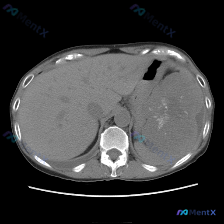

看到一个腹部CT的病例资料,影像表现非常有特点,整理一下思路和大家分享讨论。 --- 先看核心影像表现 这是一份腹部CT横断面(软组织窗)的图像: 1. 肝脏:形态大小基本正常,实质密度相对均匀,没看到明确局灶性占位。 2. 脾脏(重点):明显增大,位置下移;更关键的是,脾实质内可见大片状、不规则的...

看到一份很有思辨意义的病例资料,整理了一下影像表现和分析思路,分享给大家。 病例核心信息 - 人群:男性患者 - 主诉/主要表现:全身症状(具体描述未细化,但作为核心就诊原因) - 关键影像:腹部CT平扫横断面 影像表现拆解 这张CT平扫的核心异常非常明确,在脾脏实质中部: 1. 典型形态:病灶核心...